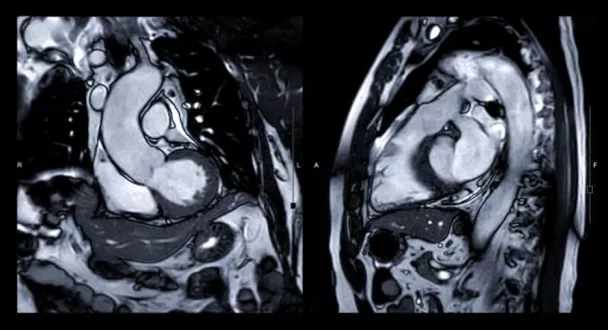

IRM cardiaque

IRM cardiaque de stress à l'Imagerie de Bois-Bernard (62)

L’IRM cardiaque de stress consiste à étudier l’anatomie du cœur pour éventuellement y détecter certaines anomalies. « Plus précisément, l’IRM cardiaque nous permet d’avoir des informations anatomiques sur la masse cardiaque, l’épaisseur du myocarde, les valves cardiaques ou encore le péricarde. Elle nous donne également des informations fonctionnelles avec des mesures d’efficacité de la pompe du cœur (calculs de volumes, de fraction d’éjection et étude de la mobilité des parois) », explique le Dr Vaquette. Quand on ajoute un stress au cœur lors de cet examen, il est alors possible d’étudier la perfusion du muscle cardiaque. « En injectant un agent pharmacologique, nous pouvons reproduire des effets semblables à ceux d’un effort. Il est alors possible de visualiser si une partie du cœur est mal oxygénée par un rétrécissement d’une artère coronaire en visualisant une diminution du flux sanguin », poursuit le cardiologue.